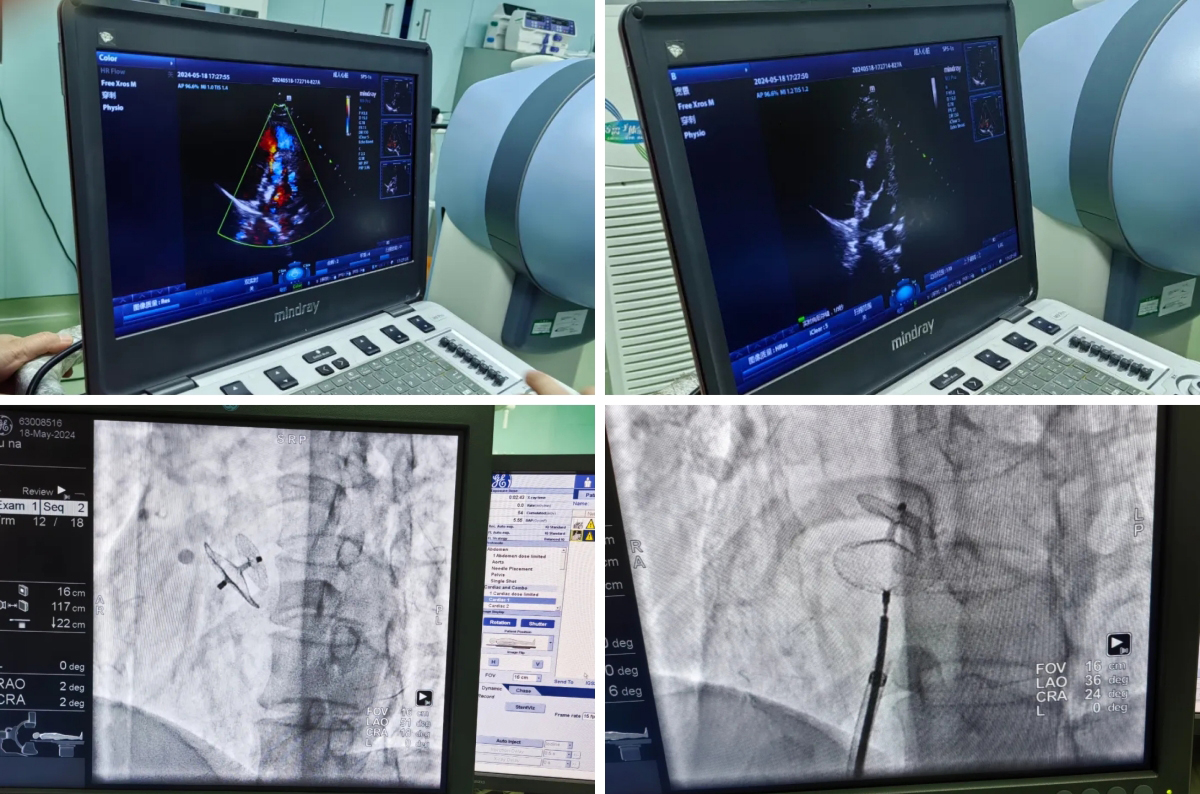

心内科、超声医学科通力协作,为患者完善检查——经胸超声、右心声学造影、经食道超声后,找到引发患者脑梗塞的“元凶”,明确诊断为“卵圆孔未闭”。为了拆除这个“定时炸弹”,避免再次发生脑梗塞,心内科乔瑞与上海瑞金医院心血管病介入专家丁风华教授进行远程会诊,通过阅片及检查报告,认为需进行介入下封堵治疗。

5月19日,在丁风华教授指导下,手术团队经食道超声下发泡试验,准确测量了隧道长度、高度,为置入封堵伞的大小精准预判,并有效预防术后并发症可能。手术过程顺利,仅用时30分钟。术后,患者头痛、头闷症状明显缓解。患者和家属拉着医护人员的手,连声说着“谢谢,谢谢!”